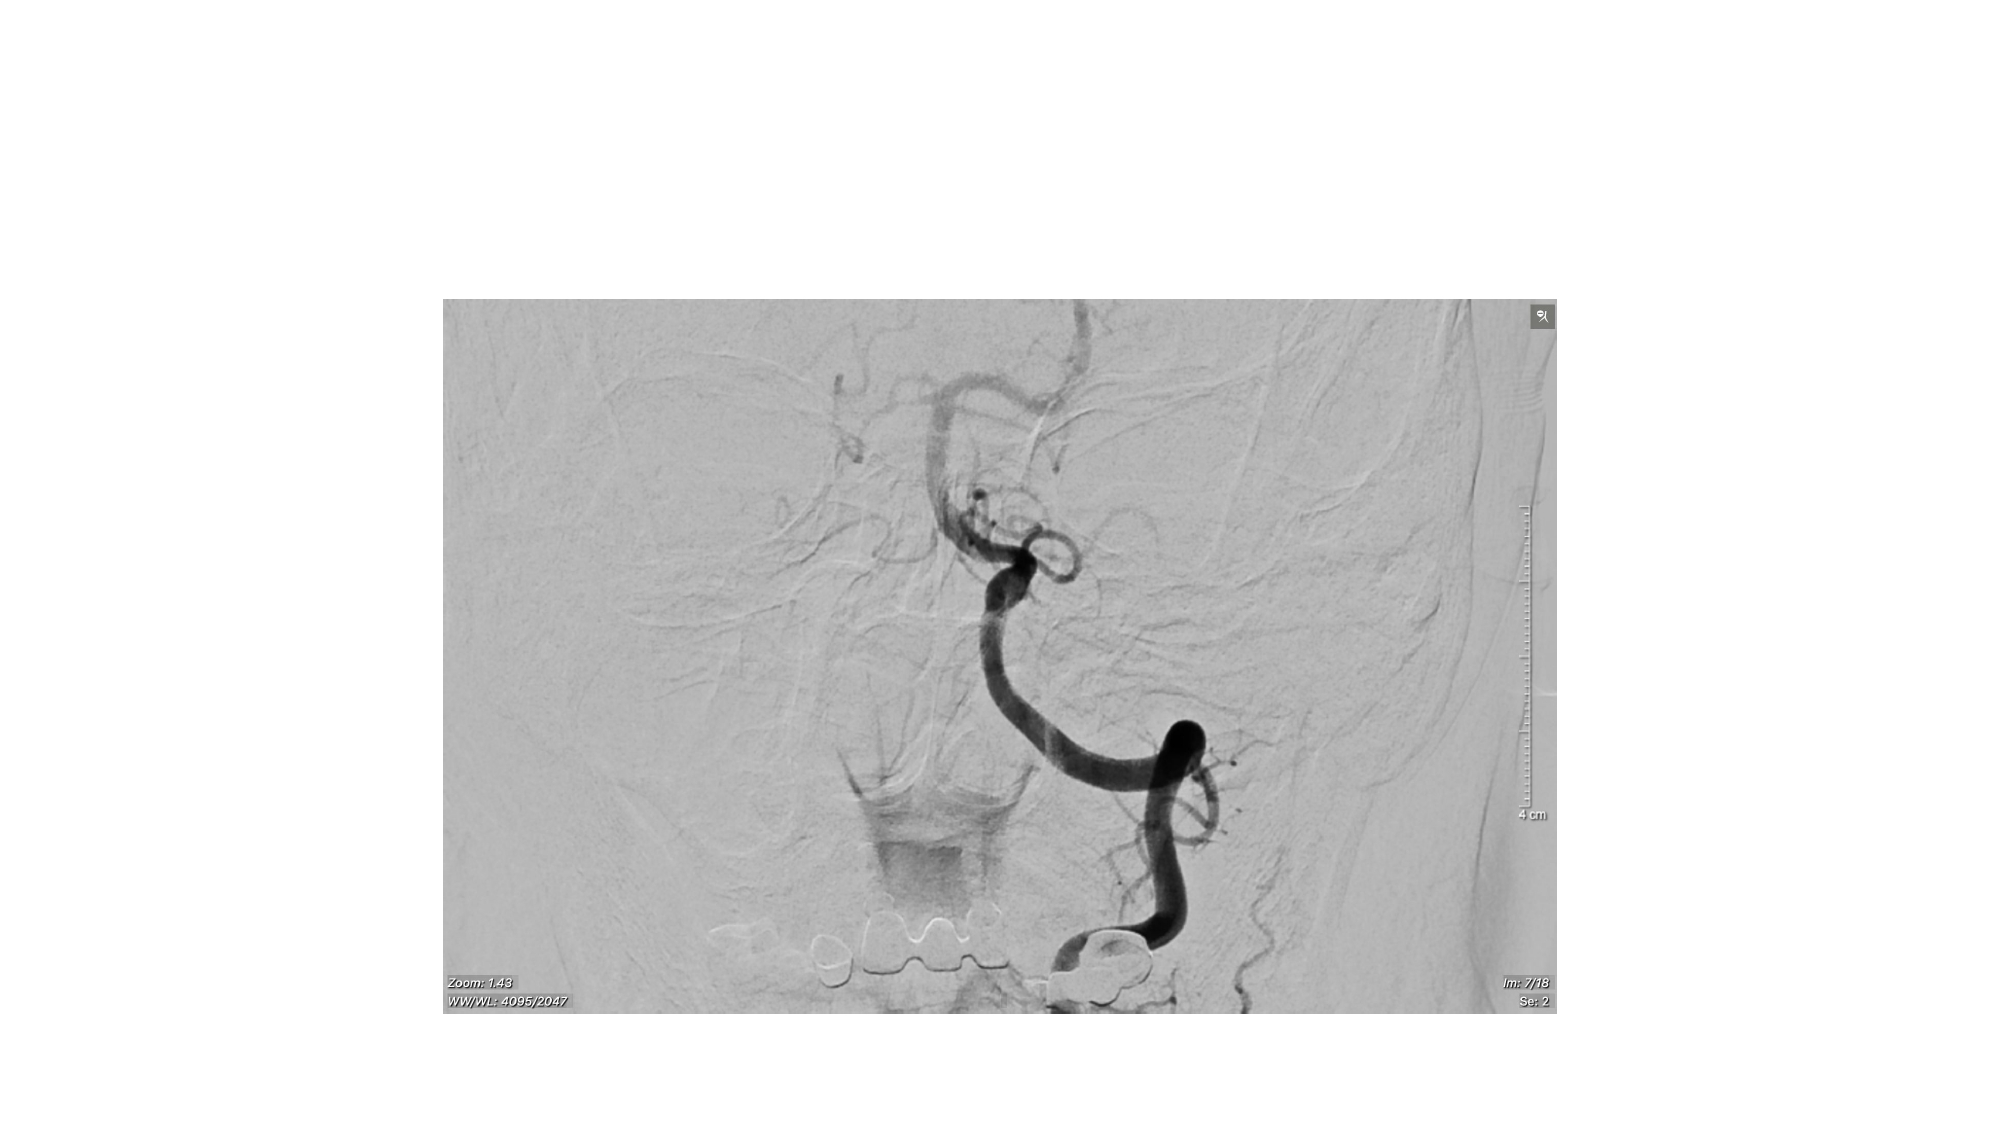

| 13:30 - 14:10 | Surgical management of skull base trauma Endovascular Management of Post-Traumatic Intracranial Vascular Lesions | Assoc. Prof. Nguyen Trong Yen Dr. Nguyen Ngoc Cuong | |

| 15:10 - 16:10 | Interactive Case Demonstration and Discussion II: ~20 minutes each, (5 minutes presentation followed by 15 minutes discussion) Practicals: How I am doing it? Participants present case presentations about how they do it? The faculty comment on and discussion. 1. Endoscopic approach in post-traumatic CSF leakage - Dr. Nguyen Thanh Xuan 2. Endovascular approach in CCF - Assoc. Prof. Le Thanh Dung | Prof. Christian Matula International & local faculties Participants | |